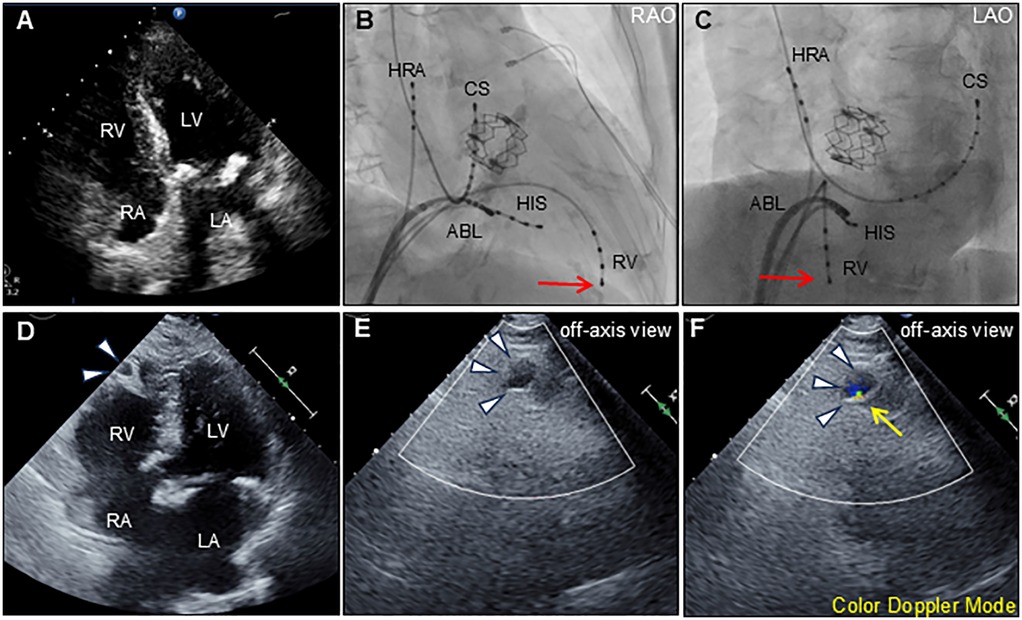

An 88-year-old woman was admitted with symptomatic paroxysmal supraventricular tachycardia that had persisted for three years. The patient had a history of severe aortic stenosis for which transapical transcatheter aortic valve replacement was performed seven years ago. Her initial vital signs were blood pressure of 79/60 mmHg and heart rate of 164 beats/min. The physical examination findings were unremarkable. Laboratory test revealed elevated serum level of brain natriuretic peptide (171.6 pg/ml, reference: <18.4 pg/ml). Electrocardiography revealed narrow QRS tachycardia with a short RP (Supplementary Figure S1A). Tachycardia was terminated with rapid intravenous administration of adenosine triphosphate (Supplementary Figure S1B). However, the patient experienced frequent paraoxymal supraventricular tachycardia episodes. Echocardiography revealed no structural or functional heart abnormalities (Figure 1A; Supplementary Video S1). Unenhanced computed tomography scans showed no biventricular abnormalities suggestive of myocardial infarction or aneurysm. An electrophysiological study was performed four days after admission. Catheters were placed in the high right atrium, the His bundle region, coronary sinus, and right ventricular (RV) apex. Premature ventricular contractions frequently occurred during RFCA, and, hence, the RV pacing catheter was held tightly to avoid the unintended catheter movement. Based on the electrophysiological study, slow/fast atrioventricular nodal reentrant tachycardia was diagnosed. Subsequent successful anatomical slow-pathway ablation was performed according to standard techniques (Figures 1B,C). We excluded any complications, including cardiac tamponade, on postprocedural echocardiography. Follow-up echocardiography revealed RV apical outpouching on postprocedural day 2 (Figures 1D–F; Supplementary Video S2). The patient was asymptomatic, and her vital signs were stable. Physical examination and electrocardiographic findings were unremarkable (Supplementary Figures S1C,D). Follow-up laboratory tests were close to normal. Differential diagnoses of ventricular outpouching include true aneurysms and pseudoaneurysms. Cardiac computed tomography angiography (CCTA) further characterized the morphology and features of the RV apical outpouching (Figures 2A–D). Note the presence of contrast-filled RV outpouching at the apex that protruded during systole, with a maximum diameter of 12.1 mm and a narrow orifice of 1.5 mm with an orifice-to-maximum diameter ratio of 12.4%, suggestive of RVP. CCTA revealed normal coronary arteries (Figures 2E,F). Pericardial effusion was not observed. A detailed review of the computed tomography images confirmed the absence of RVP before the RFCA procedure and its presence after the procedure (Figure 3). Given the temporal relationship between RFCA and the occurrence of RVP without any other identifiable cause, a final diagnosis of iatrogenic RVP was made. After multidisciplinary discussion, taking into consideration that a ventricular pseudoaneurysm is susceptible to cardiac rupture, the patient underwent urgent surgical repair of the RVP. No bleeding was observed in the pericardial sacs. There was no evidence of pericarditis, intrapericardial bleeding, or cardiac rupture except for a slight bulge at the RV apex. Epicardial echocardiography was used to identify the pseudoaneurysm, as such pseudoaneurysm was difficult to identify by visual examination. Subsequent vertical mattress suture repair with Teflon-felt reinforcement was performed for the RVP. The patient's postoperative course was uneventful, and she remained asymptomatic at the one-year follow-up (Supplementary Figure S2).

Figure 1. Transthoracic echocardiography and ablation images. Preprocedural transthoracic echocardiography (apical 4-chamber view) shows normal biventricular function with normal anatomy (A) Radiographs of the right anterior oblique [RAO; (B)] and left anterior oblique [LAO; (C)] views show the radiofrequency ablation catheter (ABL) positioned at the posterior right atrial septum. Other catheters were positioned at the high right atrium (HRA), His-bundle (HIS), coronary sinus (CS), and right ventricle (RV). Red arrows indicate the tip of the indwelling RV catheter. Postprocedural transthoracic echocardiography (apical 4-chamber view) reveals an outpouching of the right ventricular apex (arrowheads) (D) Color Doppler echocardiography using an off-axis view reveals outpouching of the right ventricular apex (arrowheads) during diastole (E) and systole (F) The expansion with the antegrade flow at systole, suggests communication between the outpouching and right ventricle (yellow arrow). LA, left atrium; LV, left ventricle; RA, right atrium; RV, right ventricle.